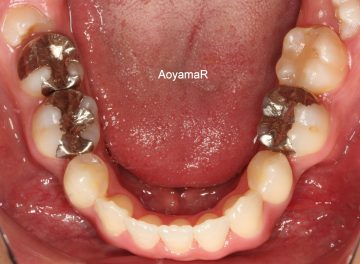

先天性欠如(生まれつき歯が足りない)の矯正症例

(23歳 女性 )

上顎両側第一小臼歯、下顎両側第二小臼歯抜歯を行い,前歯の舌側移動をマウスピース型カスタムメイド矯正装置(インビザライン)単独で行った。

治療前